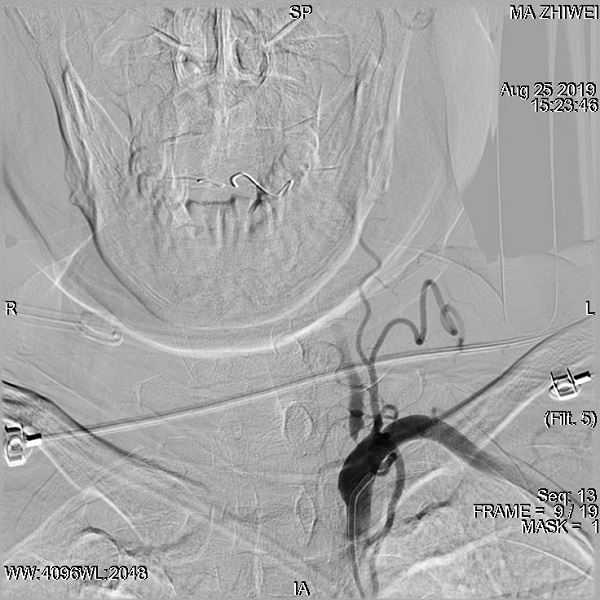

医院脑血管介入中心主任、危急重症医学科副主任、主任医师刘叶辉教授综合评估后考虑患者为急性大动脉闭塞,已经错过最佳静脉溶栓时间,患者随时可能因脑干、小脑梗死而死亡,与家属沟通后决定行介入取栓治疗。完善脑血管检查提示,左侧椎动脉起始部重度狭窄,右侧椎动脉发出大脑后下动脉以远闭塞。

予以“球囊扩张+支架植入+机械取栓”术后血管再通成功,左侧椎动脉起始部重度狭窄明显改善。